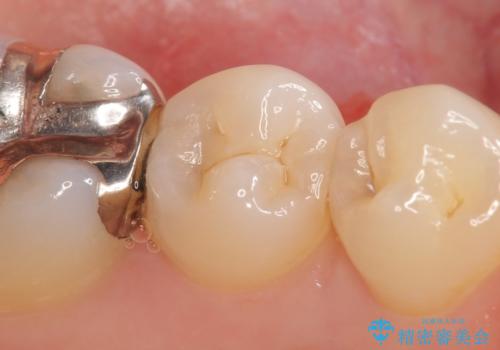

自発痛・持続痛等の症状がなく、露髄(歯の神経が露出してしまうこと)することなく虫歯の除去を完了したため、しばらく経過観察を行った後に神経治療をすることなく、セラミックインレーによる修復を行うことができました。

当院のセラミックインレーはemaxという強度と審美性に優れた材料を使用しています。

またプレス方式でインレーを製作しているため、削り出しで製作するCADCAMより優れた適合性も持ち合わせており、虫歯が再発しにくい修復物です。